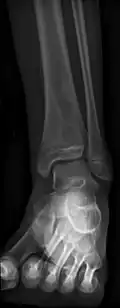

Ropień Brodiego (łac. abscessus Brodie, ang. Brodie abscess) – postać przewlekłego zapalenia kości i szpiku.

Objawia się radiologicznie centralnie położonym ogniskiem przejaśnienia otoczonym dosyć szeroką tzw. strefą sklerotyczną kości, bez ostrych granic[1]. Zazwyczaj występuje w przynasadach kości długich, w okolicy stawu kolanowego i skokowo-goleniowego. Ognisko ropne zostaje otoczone błoną i zazwyczaj nie ulega przebiciu na zewnątrz. Spotykana u starszych dzieci i dorosłych[2].